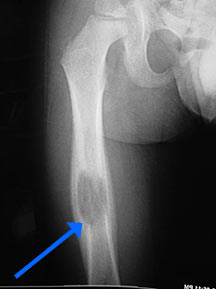

- May arise from any bone and any site within a bone (epiphyseal, metaphyseal, diaphyseal)

- Radiographically variable appearance: may appear benign (geographic) or malignant (permeative or moth eaten)

- Femur

- Curettage and bone grafting for long bones and weight bearing bones at risk for fracture